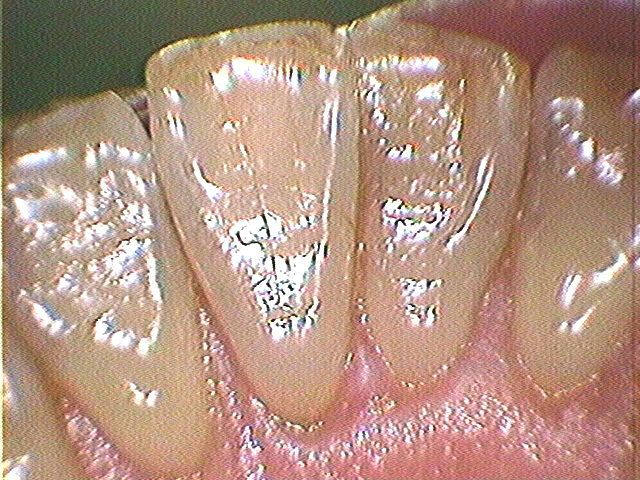

Photo-3.多量の出血

thumb-1